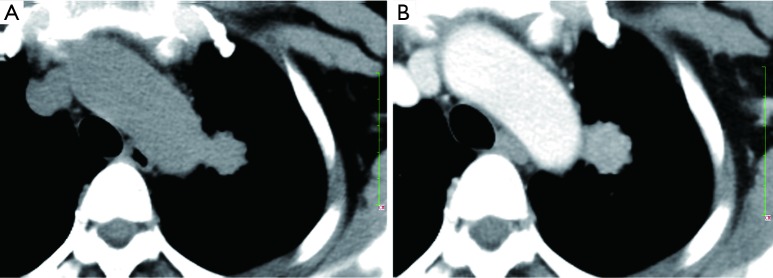

After administration of iodinated contrast material intravenously with power injection (300 mg/mL at 2 mL/sec), nodular enhancement of less than 15 HU is strongly predictive of benignity (Figure 9); whereas enhancement of more than 20 HU, reflecting presence of tumour neo-vascularisation, is indicative of malignancy (Figure 10). Results from a large multicenter study found that contrast-enhanced CT has a sensitivity of 98% and a specificity of 58% when using a cutoff of 15 Hounsfield units for enhancement (72). A recent meta-analysis of ten dynamic CT studies reported pooled sensitivity of 93%, specificity of 76%, positive predictive value (PPV) of 80% and negative predictive value (NPV) of 95% for SPN characterization (73). Higher accuracy is reported for dynamic enhancement evaluation on helical CT, by analyzing combined wash-in and washout characteristics. Malignant nodules show greater washout of contrast enhancement (74). Dual-energy CT imaging has also been used in several studies to evaluate nodules with similar diagnostic accuracy (75,76). Limitations of contrast-enhanced CT relate to its false positive results for malignancy caused by inflammatory lesions; and measurement error that can occur in evaluation of small nodules. Given that measurement of the density is difficult for heterogeneous lesions and those less than 1 cm in diameter, in practice contrast-enhanced CT only yields reliable information for homogenous nodules equal to or above 8 mm in diameter.

Figure 9.

A small subpluera nodule (15 mm × 10 mm; arrow) with well-defined margin and enhancement of 16 Hounsfield units after CT contrast agent injection, pathologically proved to be a cryptococcal granuloma. (A,B): plain CT; contrast enhanced CT.

Figure 10.

A pulmonary carcinoma (arrow) with enhancement of 37 Hounsfield units after CT contrast agent injection. (A) plain CT; (B) contrast enhanced CT.